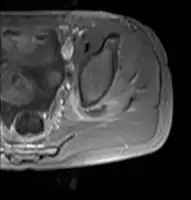

| Transverse T2 magnetic resonance imaging section through the hip region showing abscess collection in a patient with pyomyositis. | |

Axial T1 weighted fat suppressed post IV gadolinium contrast enhanced MRI image showing a mutliloculated bacterial abscess in the left gluteal muscle which grew Staphylococcus aureus (methicillin sensitive) thought to be due to tropical pyomyositis.

Coronal fat suppressed post contrast image showing a multiloculated bacterial abscess in the left gluteus minimus muscle due to tropical pyomyositis.

Coronal T2 weighted fat suppressed image showing a multiloculated fluid collection in the left gluteal musculature due to tropical pyomositis in a 12-year-old boy.